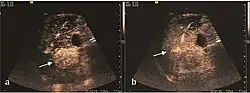

HCC appearance on 2D ultrasound is that of a solid tumor, with imprecise delineation, with heterogeneous structure, uni- or multilocular (encephaloid form). An "infiltrative" type is also described which is difficult to discriminate from liver nodular reconstruction in cirrhosis. Typically HCC invades liver vessels, primarily the portal veins but also the hepatic veins . Doppler examination detects a high speed arterial flow and low impedance index (correlated with described changes in tumor angiogenesis). The spatial distribution of the vessels is irregular, disordered. CEUS examination shows hyperenhancement of the lesion during the arterial phase. During the portal venous phase there is a specific "wash out" of ultrasound contrast agent (UCA) and the tumor appears hypoechoic during the late phase. Poorly differentiated tumors may have a stronger wash out leading to an isoechoic appearance to the liver parenchyma during portal venous phase. This appearance was found in approx. 30% of cases. The described changes have diagnostic value in liver nodules larger than 2 cm.

These lesions have various patterns (hypo or hyperechoic) with at least 1 cm diameter. They are hepatocytes with dysplastic changes, but without clear histological criteria for malignancy. They are divided into low-grade dysplastic nodules, where cellular atypia are mild and high-grade dysplastic nodules with moderate or severe cellular atypia, but without any established signs of malignancy. Occasionally, well-differentiated HCC foci can be identified in high-grade dysplastic nodules (appearance called "nodule in nodule") . Most authors accept the carcinogenesis process as a progressive transformation of DN from low-grade to high-grade and into HCC. The nodule's vasculature changes progressively, correlated with the degree of malignancy, and it is characterized by decrease until absence of portal venous input and by increase of arterial intratumoral input. Neoformation vessels occur with increasing degree of dysplasia. Arterial neovascularization is enhanced in a chaotic and explosive way, while normal, arterial and portal vasculature continues to decline. High-grade dysplastic nodules are hypovascularized both arterial and portal phases, while early HCC nodules may have similar arterial pattern with the surrounding parenchyma or exacerbated, and portal hypovascularization. In moderate or poorly differentiated HCC (classic HCC) tumor nutrition is performed only by neoformation vessels (abundant), the normal arterial and portal vasculature completely disappearing. This behavior of intratumoral vascularization is typical for HCC and is the key to imaging diagnosis.

B-mode ultrasonography is unable to distinguish between regenerative nodules and borderline lesions such as dysplastic nodules and even early HCC. Doppler examination also has a low sensitivity in differentiating dysplastic nodules from early HCC. Doppler signal may be absent in both regenerative and dysplastic nodules. Some authors indicate the presence of venous type Doppler flow which reflects the portal venous nutrition of the nodule as a characteristic feature of dysplastic nodules and early HCC (Minami & Kudo, 2010). Other authors noticed the presence of an arterial flow with small frequency variations and a normal resistivity index. On CEUS examination both RN and DN may have quite a variable enhancement pattern. Generally, both nodules enhances identically with the surrounding liver parenchyma after UCAs injection. Dysplastic nodules are hypovascular in the arterial phase. In case of highgrade dysplastic nodule sometimes a hypervascularization can be detected, but without associating "wash out" during portal and late CEUS phases. In these cases, biopsy may clarify the diagnosis.

The suggestive appearance of early HCC on 2D ultrasound examination is that of hypoechoic nodule, with distinct pattern, developed on cirrhotic liver. Hypoechoic appearance is characteristic of moderate/poorly differentiated HCC, with low or absent fatty changes. Rarely, HCC may appear isoechoic, consist of a tumor type with a higher degree of differentiation and therefore with slower development. Another common aspect is "bright loop" or "nodule-in-nodule" appearance, hypoechoic nodules in a hyperechoic tumor.

On CEUS examination, early HCC has an iso- or hypervascular appearance during the arterial phase followed by wash out during portal venous and late phase. There are studies showing that the wash out process is directly correlated with the size and features of neoplastic circulatory bed. Thus, highly differentiated HCC illustrates the phenomenon of late or even very late "wash out" while poorly differentiated HCC has an accelerated wash out at the end of arterial phase. It is therefore mandatory to analyze all these three phases of CEUS examination for a proper characterization of liver nodules. Tumor wash out at the end of the arterial phase allows the HCC diagnosis with a predictability of 89.5%. Some authors consider that early pronounced contrast enhancement of a nodule within 1–2 cm developed on a cirrhotic liver is sufficient for HCC diagnosis. These results prove that for a correct characterization of the lesions it is necessary to extend the examination time to 5 minutes or even longer.